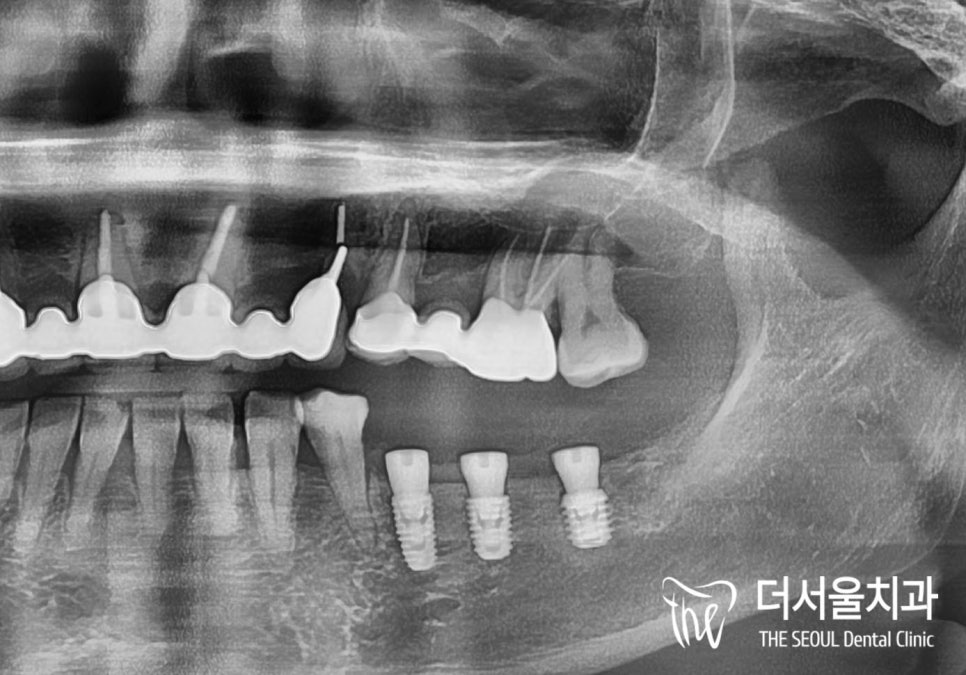

4. 픽스처 식립

환자도 가수면 상태에 도달하여

안정된 상태이고,

철저한 멸균 환경에서 제가 생각한 위치에

인공치근을 심으면

수술은 금방 끝이 납니다.

제가 들인 시간은…

인공치근을 3개나 심었지만…

15분……?

5. 마무리

충분히 회복된 후

파노라마 촬영이 끝나면

수술이 얼마나 잘 되었는지 보여드립니다.

이후에는 인공치근이

본인의 턱뼈에 잘 유착될 수 있도록

2~3개월 정도 기다려 준 뒤에

개인 맞춤형 크라운을 올리면

정말로 끝납니다!!

아주 예쁘게 잘 완성됐죠?

치료기간 2022.12.13 ~ 2023.04.06